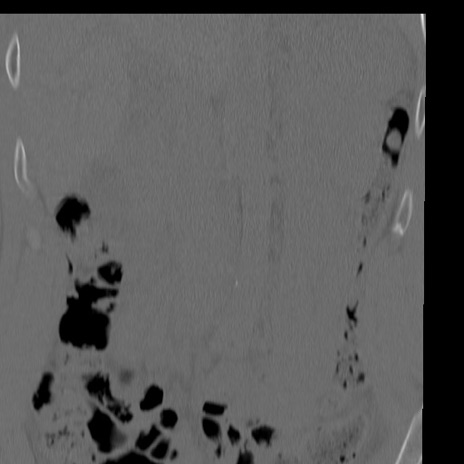

症例3 腰椎CT(冠状断像)

腰椎CT